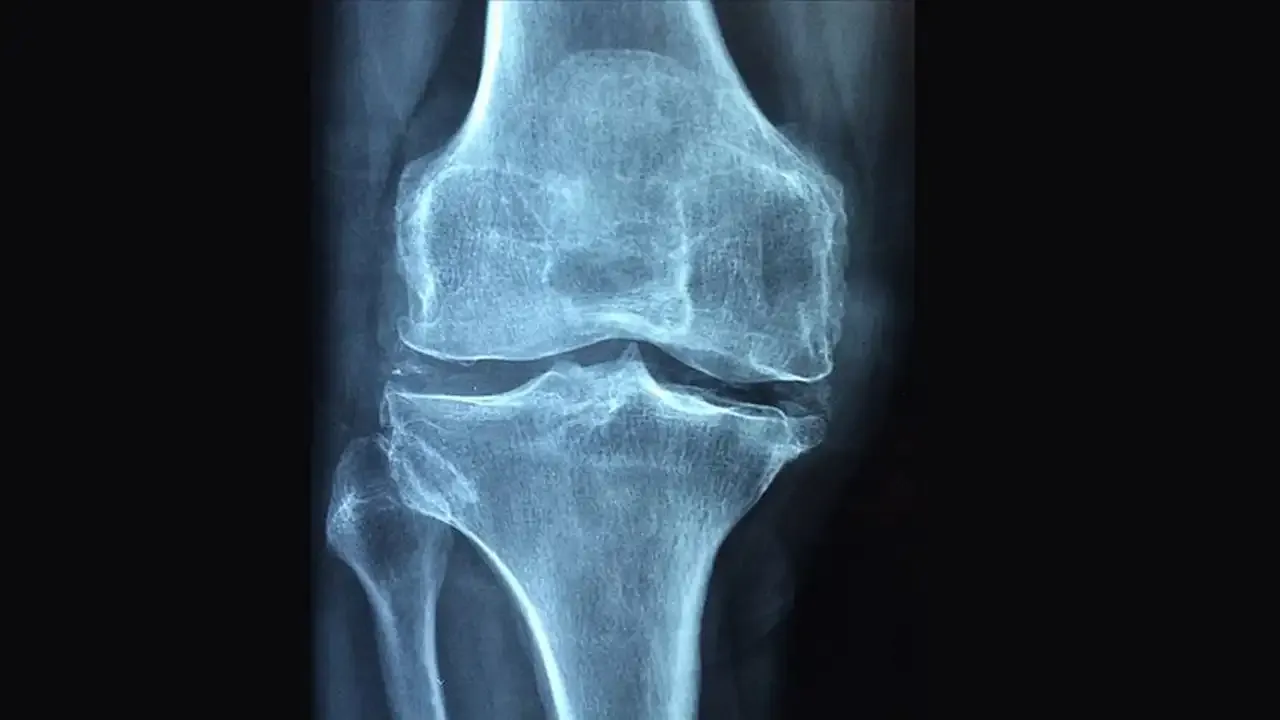

Kemik mineral yoğunluğu ölçümü (DEXA), osteoporozun erken tespiti için en güvenilir yöntemdir. Genel olarak 65 yaş ve üzeri tüm kadınlara ve 70 yaş ve üzeri erkeklere kemik taraması öneriliyor. Ancak menopoz sonrası kadınlar, düşük vücut kitle indeksine sahip olanlar, daha önce kırık yaşamış bireyler, uzun süre kortizon gibi kemik sağlığını etkileyen ilaç kullananlar ve aile öyküsünde osteoporoz bulunan kişiler için bu tarama 50 yaşından itibaren yapılabilir.

Erken tanı, hastalığın yol açabileceği kırıkları önlemede ve kemik sağlığını korumada hayati öneme sahiptir. Düzenli kemik yoğunluğu ölçümü ve doktor kontrolleri, hastalığın kırık oluşturmadan önce fark edilmesine ve uygun önlemlerin alınmasına yardımcı olur.